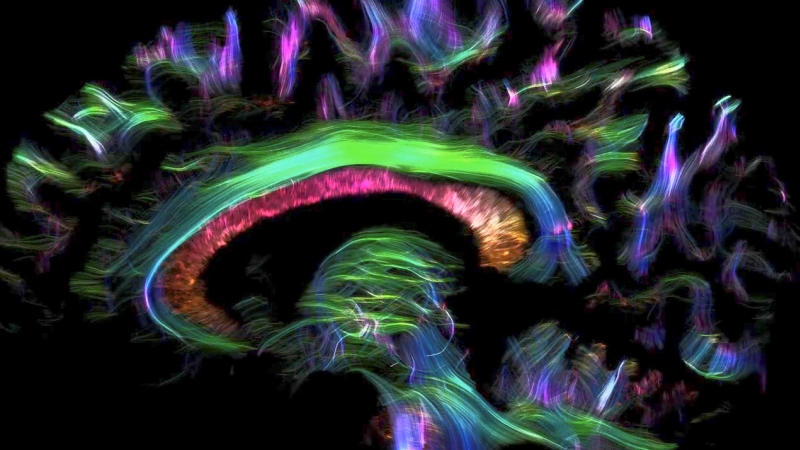

Advanced brain mapping to personalize epilepsy care

Sophisticated imaging technology that uses higher magnet strengths and computational tools allow Mayo Clinic doctors to identify where seizures originate within 1 millimeter. In the past, physicians may have been unable to identify the small lesions or abnormalities in the brain that caused their epilepsy.

Mayo Clinic’s surgeons are also pioneering new treatments for epilepsy to reduce or cure seizures beyond traditional medication. These treatments include neuromodulation, laser surgery and temporal lobectomy. Mayo Clinic is one of the few centers in the country that offers the newly FDA-approved deep brain stimulation for the treatment of refractory epilepsy.